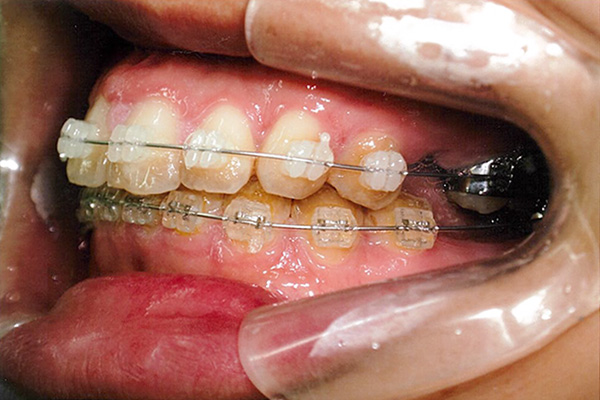

3ヶ月後

10ヶ月後

24ヶ月後

42ヶ月後